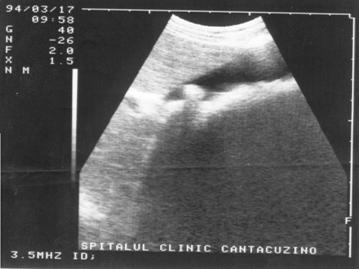

Spatiul fizic de separare dintre structuri sau tesuturi cu densitati diferite (respectiv impedante acustice diferite) se numeste interfata. Interfata este cu atat mai evidenta cu cat diferenta dintre densitatea tisulara este mai mare. De exemplu, limita de separatie intre chiste si tesuturile solide invecinate este foarte evidenta; de aceea chisturile din interiorul unui parenchim sunt vizibile ecografic chiar la dimensiuni mici. Foto I 62 (chist).

Figura 1. Vezica urinara

Figura 2. Chist renal stang situat in treimea medie

Figura 3. Chist ovar drept

Figura 4. Chist hepatic